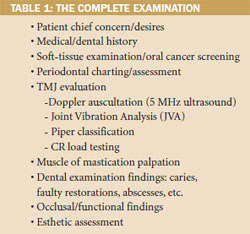

The first step is the performance of a full examination; it is complete when the clinician has identified all potential causes of poor oral health or function (Table 1). The seven goals of complete dentistry,1 as described by Dawson, are: 1) freedom from disease in all masticatory structures; 2) maintainable healthy periodontium; 3) stable temporomandibular joints (TMJs); 4) stable occlusion; 5) maintainable healthy teeth; 6) comfortable function; 7) optimum esthetics.

The complete examination is supplemented with vital diagnostics including full-mouth and panorex radiographs, CT/MRI (if appropriate), photographs, study models, and facebow and CR bite records. The clinician should search for stability and instability during the examination (Table 2). The TMJs are considered stable for occlusal therapy if any noted disorders are extracapsular or involve only lateral pole disk displacement (Piper TMJ Class IIIB or lower). If medial pole derangement of the articular disk is diagnosed (Piper Class IVA or higher), then long-term splint therapy is considered appropriate before changing the occlusion. With a complete examination, most temporomandibular disorders can be stabilized; failure to address this issue prior to treatment may have devastating effects on newly placed porcelain restorations.4-6